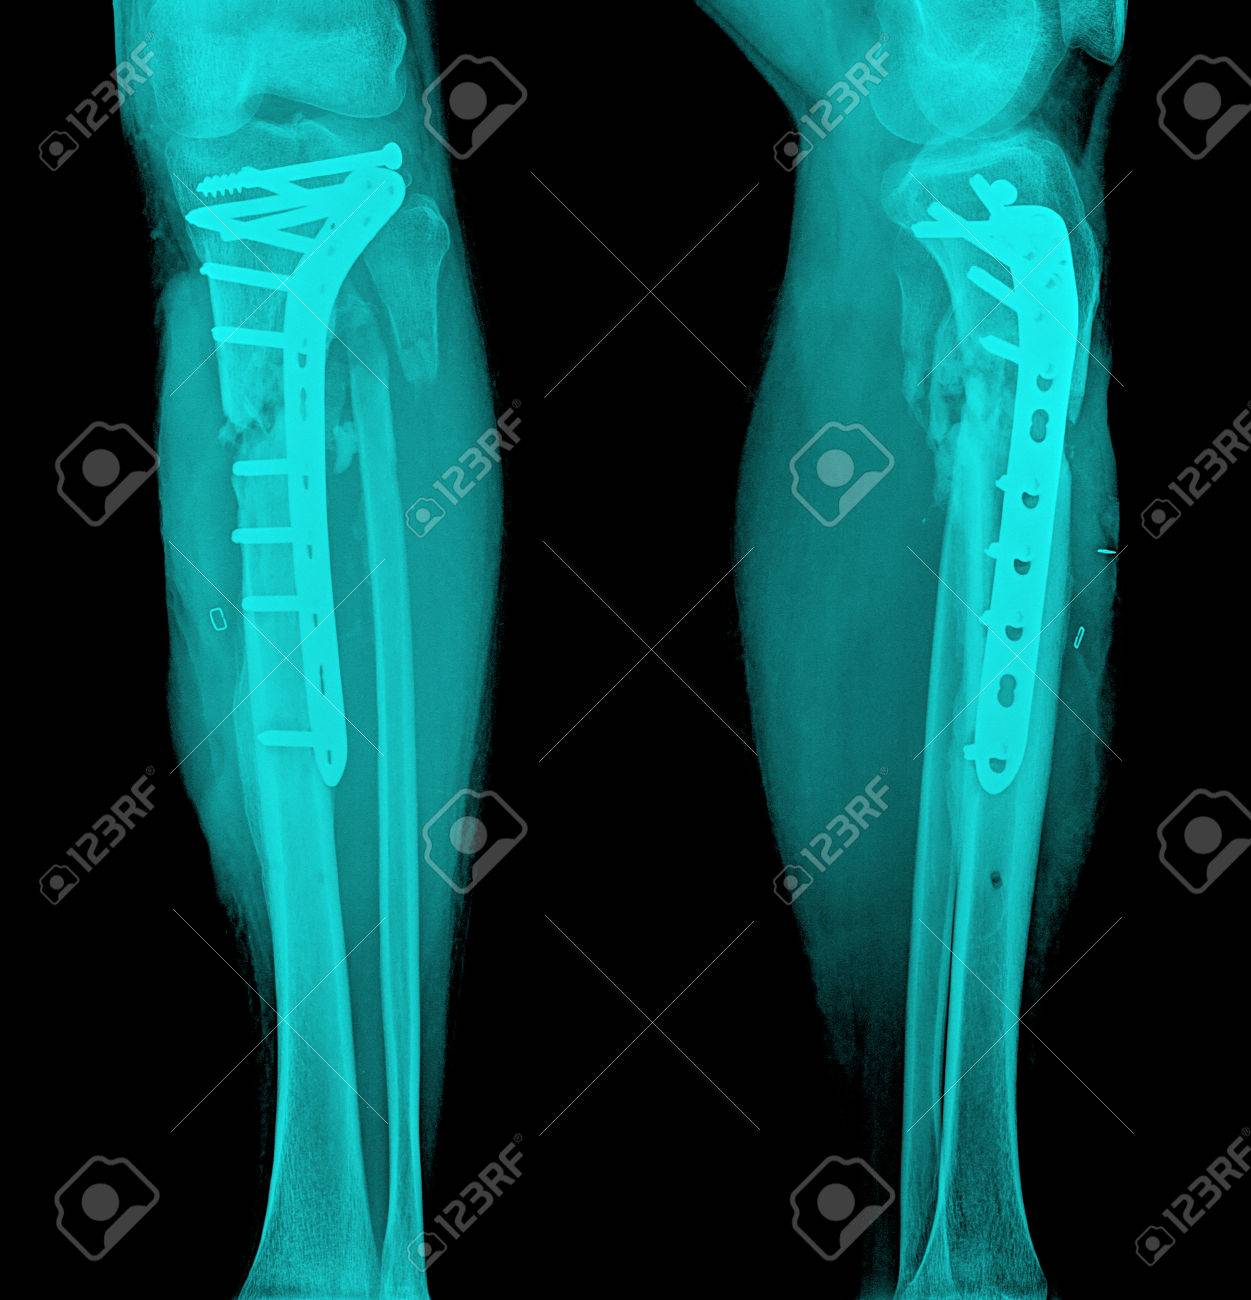

Immagini Stock Pellicola Gamba Ap Laterale Spettacolo Albero Frattura Di Tibia E Perone Osso Della Gamba Paziente E Stato Operato E Inserire Piatto E Vite Per Osso Fix Gamba Image 39099942

Immagini Stock Pellicola Gamba Ap Laterale Spettacolo Albero Frattura Di Tibia E Perone Osso Della Gamba Paziente E Stato Operato E Inserire Piatto E Vite Per Osso Fix Gamba Image 39099830